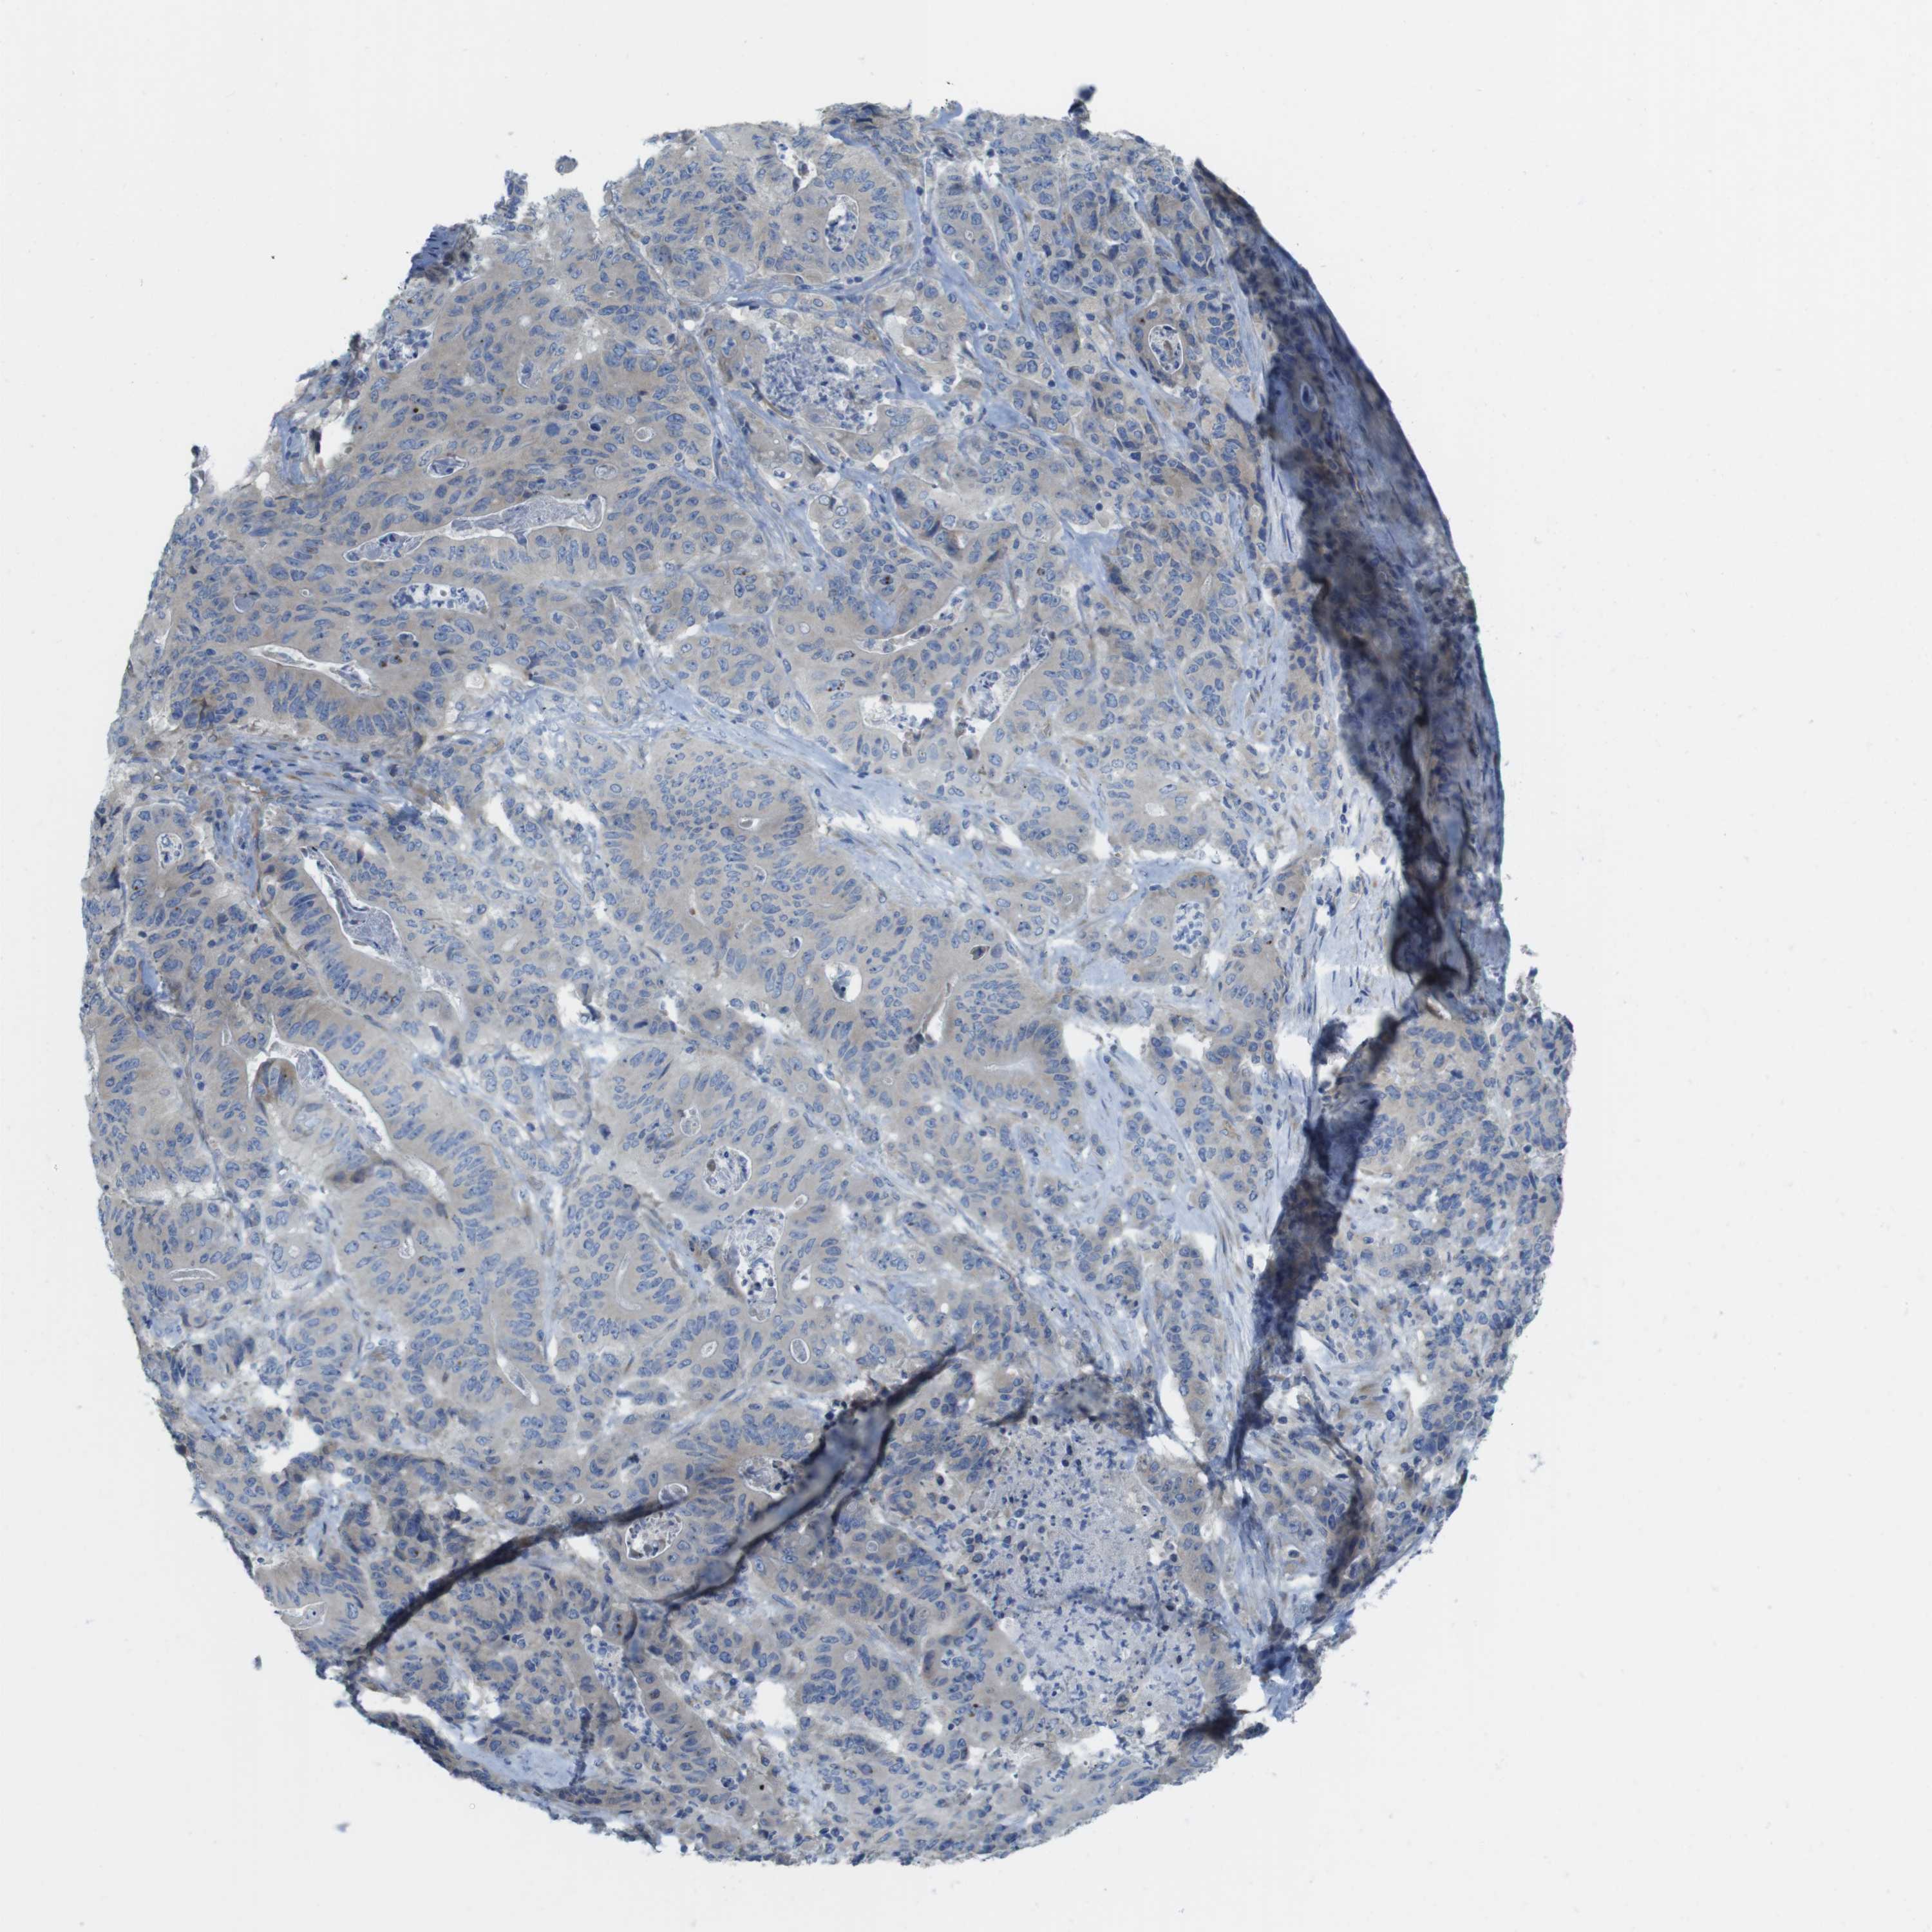

STOMACH CANCER - Protein expressioni

A mouse-over function shows sample information and annotation data. Click on an image to view it in a full screen mode. Samples can be filtered based on level of antibody staining by selecting one or several of the following categories: high, medium, low and not detected. The assay and annotation is described here.

Note that samples used for immunohistochemistry by the Human Protein Atlas do not correspond to samples in the TCGA dataset.

Antibody stainingi

Antibody staining in the annotated cell types in the current human tissue is reported as not detected, low, medium, or high, based on conventional immunohistochemistry profiling in selected tissues. This score is based on the combination of the staining intensity and fraction of stained cells.

Each image is clickable and will lead to virtual microscopy that enables deeper exploration of all samples and also displays staining intensity scores, fraction scores and subcellular localization as well as patient and tissue information for each sample.

Antibody HPA015049

Staining

High

Medium

Low

Not detected

Intensity

Strong

Moderate

Weak

Negative

Quantity

>75%

75%-25%

<25%

None

Location

Nuclear

Cytoplasmic/membranous

Cytoplasmic/membranous,nuclear

Adenocarcinoma, NOS